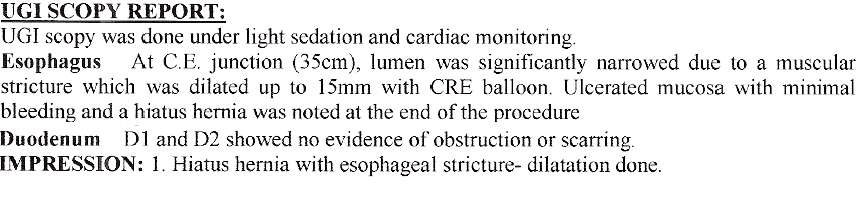

3. Difficulty in swallowing : This is considered as a serious symptom at any age group.

Difficulty in Swallowing

This can be due to severe acidic ulcerations, narrowing of the food passage due to non cancer or

cancerous lesion or pressure on the food pipe from outside.

Strong contractions of the food pipe is known as dysmotility of esophagus and an unusual condition known

as Achalasia Cardia due to powerful contraction of the valve of the esophagus at its lower end which

can cause difficulty in swallowing.

Achalasia Cardia - Balloon Dilatation

Achalasia Cardia - Balloon Dilatation

Achalasia Cardia - Balloon Dilatation

Achalasia Cardia - Balloon Dilatation